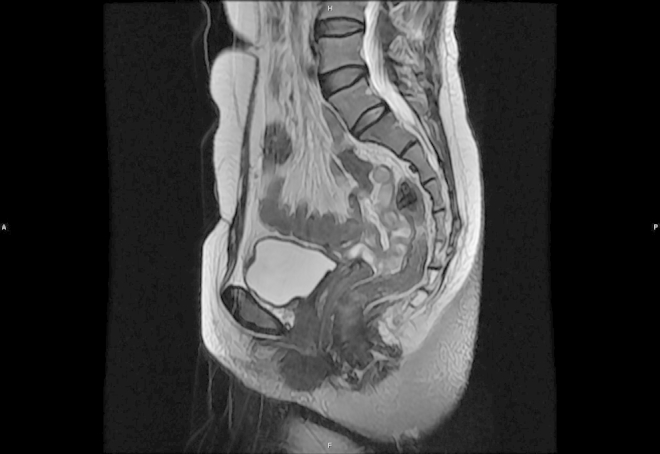

Magnetic resonance imaging (MRI) revealed the presence of a 3 × 4 × 3 cm mass which displaced the urethra laterally. The mass showed a slightly heterogenous low signal intensity on the T2-weighted images (Fig. 1). The mass displayed uniform enhancement with gadolinium administration (Fig. 2).

Figure 1.

MRI showed a mass arising from anterior wall of the vagina.